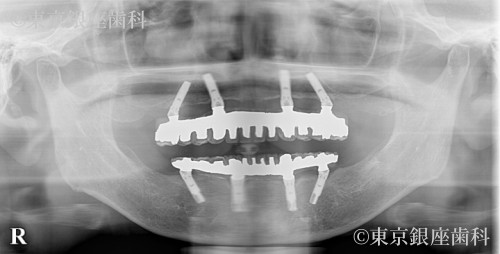

ブリッジ部の歯周病悪化から上下インプラントで噛める機能を回復した60歳代女性の症例

Before

上下ブリッジの歯周病悪化・口臭・動揺・痛みに悩んでいたが、下顎から順次インプラントを実施し改善。上下で安定した噛み合わせを獲得。

上下ワンデイインプラント(段階治療)